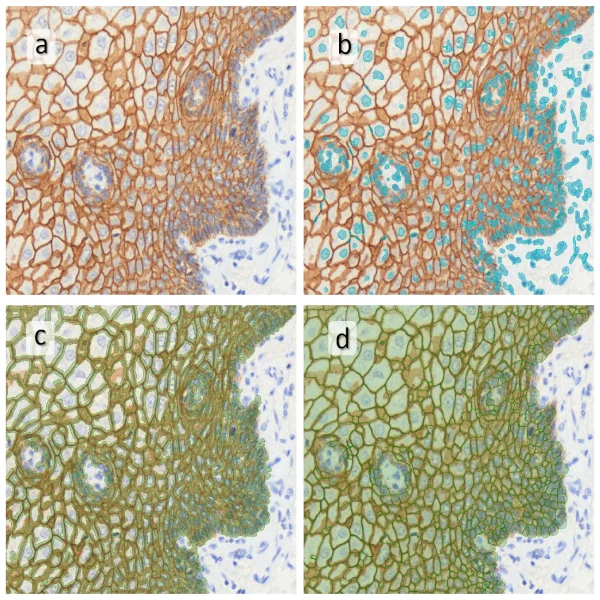

In the first example, StrataQuest was utilized to analyze a TMA sample stained for hematoxylin (blue) and for E-cadherin present in the cell membranes of epithelial cells (brown). On the original image (a), E-cadherin is shown in brown and nuclei in blue. The aim was to detect the nuclei, the epithelial cells and the membranes of epithelial cells. The challenge with this analysis was that some cells do not contain nuclei.

Image (b) shows detected nuclei, covered by nuclei mask in light blue. Next only membranes were detected (c), which are shown in green; (d) shows the detection of the whole E-cadherin+ epithelial tissue, also marked in green.

In image (e) only cells with nuclei are identified, and the whole cell with the membrane is shown in blue, while the nuclei are covered by the light blue nuclei mask; (f) represents the nuclei in light blue and the total membranes in red.